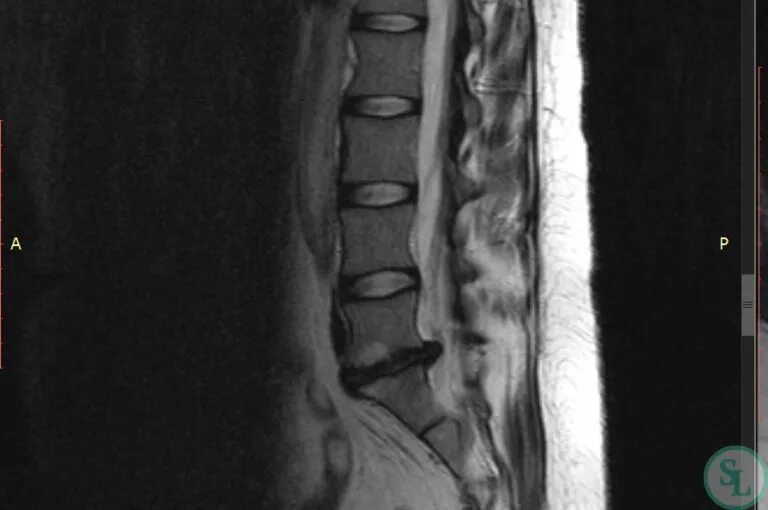

L5 s1 как лечить